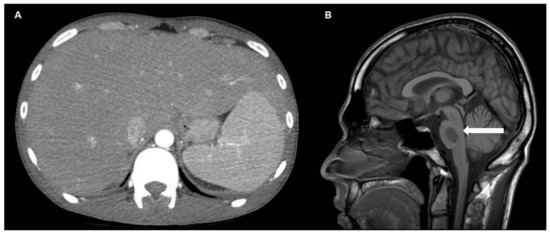

2. Case Report